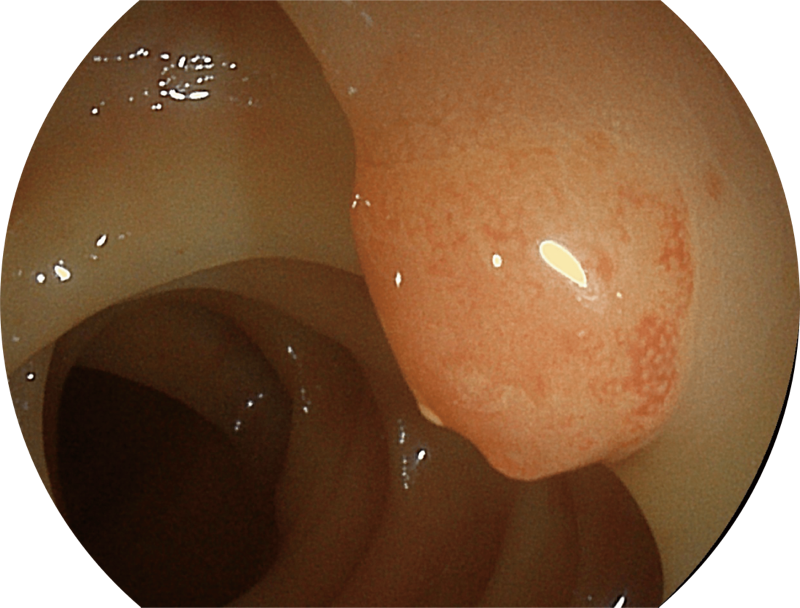

白光图像

能够凸显黏膜浅层血管轮廓和黏膜表面微结构,适用于中、近景观察下的早癌精确诊断。